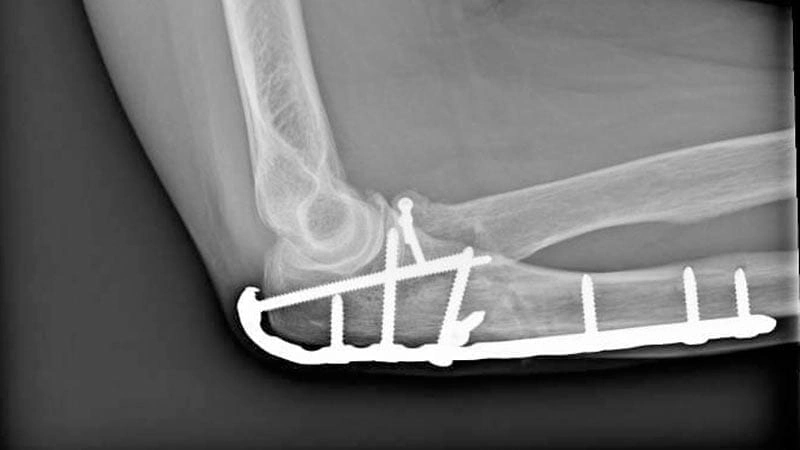

Total Dirsek Artroplastisi

Hastaların özel problemlerini yok etmek amacıyla modern tıbbın en son imkanlarından faydalanarak tedaviler uygulanmaktadır. Total dirsek artroplastisi tedavisiyle, dirsek sorunları yaşayan hastaların hayatlarına tekrardan çok daha güçlü ve sağlıklı şekilde sarılabilmeleri sağlanır. Bu noktada dirsek cerrahisi uzmanı tarafından, tüm dünyada en son uygulanan teknolojilerden faydalanılarak artroplasti protez dirsek ameliyatı yapılır. Ameliyat sonrasında da Avicenna Hastanesi uzman hekimleri hastaları takip eder ve dirsek ameliyatı sonrası gündelik yaşamlarına çok daha hızlı şekilde dönebilmeleri için destek verir.